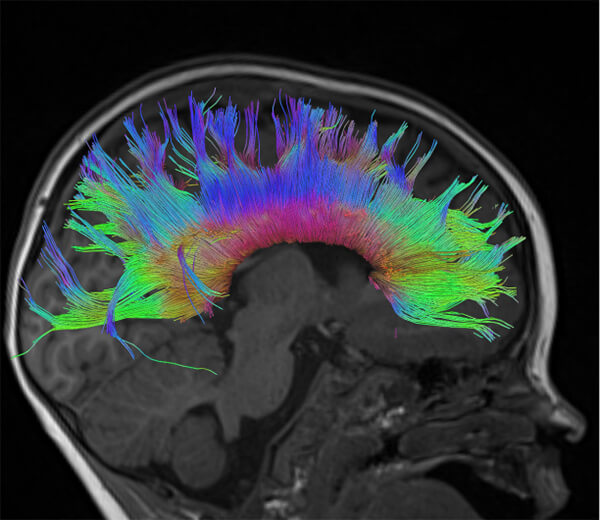

- Ειδικές τεχνικές state-of-the-art (Λειτουργική / Πολυπαραμετρική MRI, Φασματοσκοπία, Δεσμιδογραφία, Δυναμικές Αγγειογραφίες, Νευρογράφημα, Μελέτη Ροής ΕΝΥ)

- Ενσωμάτωση των δεδομένων σε συστήματα νευροπλοήγησης, ώστε ο νευροχειρουργός να αποφεύγει κατά την διάρκεια του χειρουργείου τα λειτουργικά κέντρα του εγκεφάλου (π.χ. κέντρο λόγου και κίνησης) και τη μόνιμη νευρολογική βλάβη

- Δεσμιδογραφία (Τractography)